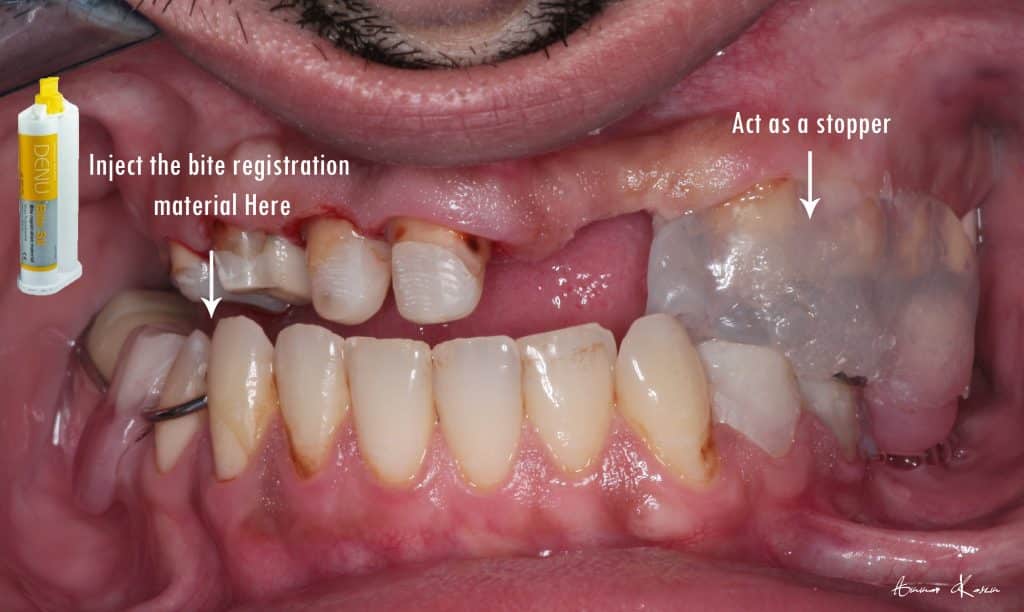

7- Preparation phase through half arch technique to preserve the vertical dimension

4- Facebow records and mounting on semi adjustable articulator

Temporization phase including;

5- 1st mock up ( edge to edge ) for 2 months

6- 2nd mock up ( Normal class I) for 3 months